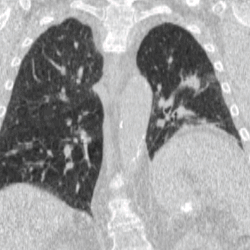

Four-dimensional computed tomography (4DCT) is a type of CT scanning which records multiple images over time. It allows playback of the scan as a video, so that physiological processes can be observed and internal movement can be tracked. The name is derived from the addition of time (as the fourth dimension) to traditional 3D computed tomography. Alternatively, the phase of a particular process, such as respiration, may be considered the fourth dimension.[1]

4DCT is used in radiation therapy planning to reduce doses to healthy organs such as the heart or lungs. Most radiation therapy is planned using the results of a 3D CT scan. A 3D scan largely presents a snapshot of the body at a particular point in time, however due to the time of the acquisition, in which the patient is likely to have moved in some way (even if only breathing), there will be an element of blurring or averaging in the 3D scan.[6] When it comes to treatment planning, this motion can mean there is less accuracy in the positioning of treatment beams, and reduce the likelihood of a repeatable set-up on the linear accelerator when it comes to treatment.[7]

To minimise physical movements of the patient, some sort of immobilisation is typically used. To overcome physiological motion, such as breathing, 4DCT acquires images at a range of times and positions, allowing the extent of motion to be visualised (e.g. from maximum inspiration to maximum exhalation). The treatment plan can then be designed with a knowledge of the full range of possible positions of important organs, and the tumour (target) itself.[8]